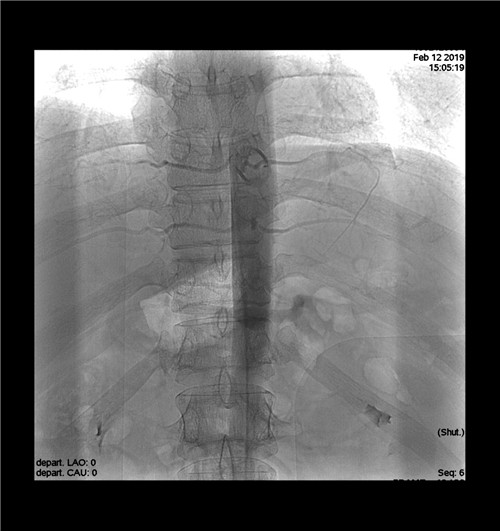

術(shù)后造影查看無(wú)血管并發(fā)癥